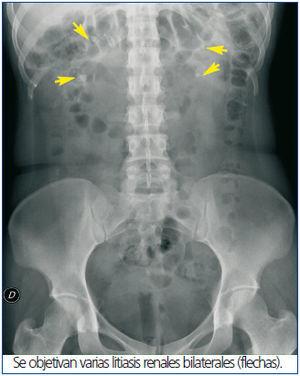

Presentamos el caso de una mujer de 28 años, gestante de 7 semanas que acudió a urgencias por debilidad intensa en el contexto de vómitos con dolor abdominal. Tenía antecedentes de rabdomiolisis secundaria a hipopotasemia severa no filiada, nefrolitiasis y nefrocalcinosis bilateral (figura 1). Se revisaron sus analíticas previas objetivando desde hace varios años una acidosis metabólica hiperclorémica y hipopotasemia con un pH urinario persistentemente alcalino. A su llegada a urgencias presentaba: TA 103/71 mm Hg, FC 78 sístoles, a la palpación abdominal profunda dolor en hipocondrio izquierdo y fosa renal izquierda y puño percusión renal izquierdo positivo.

Se solicitó una ecografía renal informada de dilatación pielocalicial del riñón izquierdo grado II-III/ IV y presencia de líquido con tractos en el espacio perirrenal izquierdo (figura 2). Útero gestante con feto vivo en su interior. Se avisó al servicio de Urología que decidió colocar un catéter ureteral doble J izquierdo, consiguiendo hacerse paso a través de una litiasis ureteral izquierda y objetivando salida de orina de aspecto purulento. Posteriormente se inició tratamiento antibiótico y aporte intravenoso de potasio y bicarbonato consiguiendo una mejoría clínica. En base del cuadro clínico, las alteraciones analíticas previas y actuales se le diagnóstica de acidosis tubular renal distal (ATD).

Figura 1. Radiografía simple de abdomen.